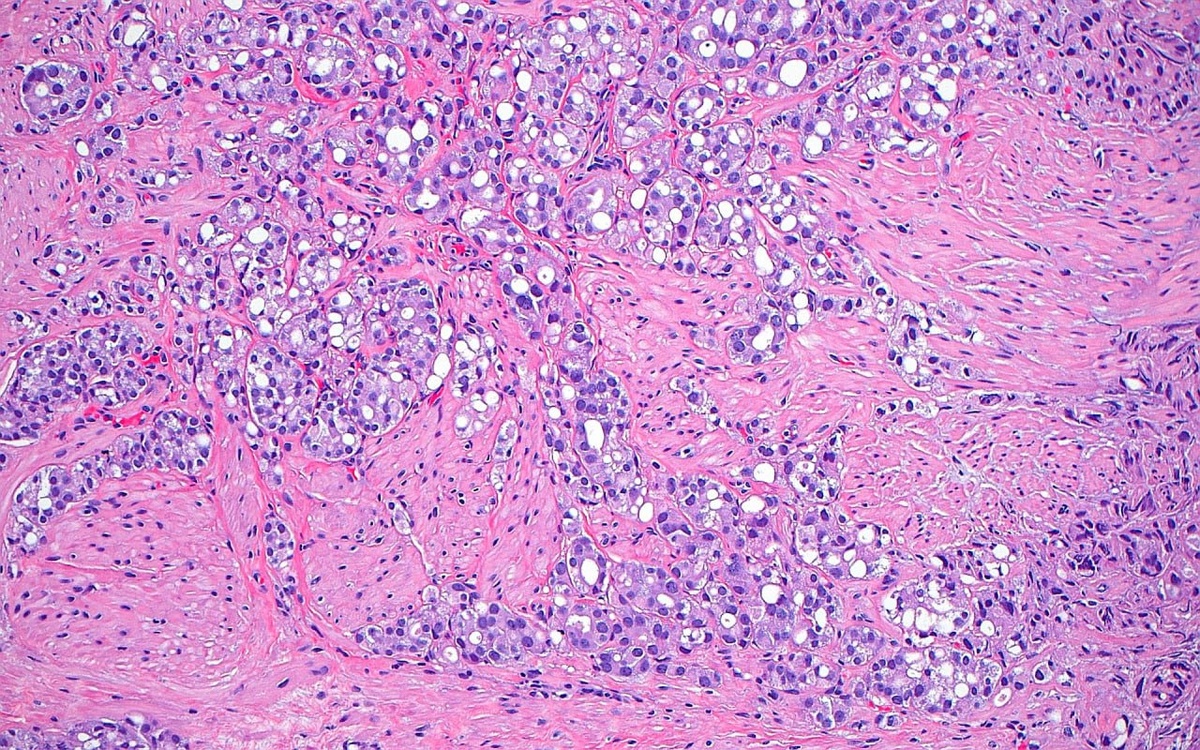

Рак предстательной железы, поражающий гладкомышечные пучки шейки мочевого пузыря.